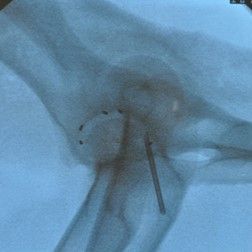

Hüftgelenksdysplasie

Das HD-Röntgen ist ein wichtiges Verfahren, um Veränderungen der Hüftgelenke zu erkennen.